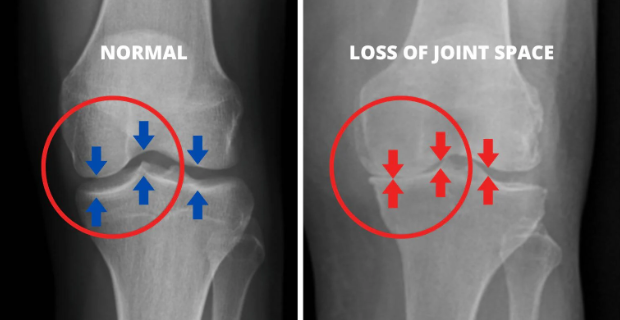

Bone-on-bone arthritis. That's what doctors call it when your cartilage is completely gone.

These weren't mild cases. Bone-on-bone. X-rays showing almost no cartilage. They'd exhausted every option – physical therapy, injections, medications, everything.

As cartilage wears away over time, bones start rubbing against each other, causing that grinding, bone-on-bone pain. This friction leads to inflammation, swelling, stiffness – especially in the morning – and a significant reduction in your mobility and independence.